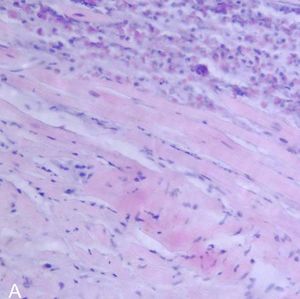

| صورة نسيجية لالتهاب فيروسي لعضلة القلب في عملية تشريح لمريض مصاب بالمرض. | |

يتم كشف التهاب العضلة القلبية عن طريق استخدام مخطط القلب الكهربائي(ECG)،وهناك أيضاً علامات للالتهاب من عدم انتظام تركيز الكرياتين (creatine)، والتروبونين (troponin). ويمكن كشفها أيضاً عن طريق عمل القسطرة، بحيث يتم عمل فحص لنسيج القلب، بحيث يتم أخذ عينة صغيرة من النسيج الداخلي والخارجي للقلب، ويتم فحصها من قبل مختص أمراض من خلال مجهر ضوئي. حديثاً، أصبح بالإمكان الكشف من خلال استخدام جهاز الأشعة المغناطيسية لمنطقة القلب (cMRI: Cardiac Magnetic Resonance Image)، وقد تبين أنها طريقة نافعة.